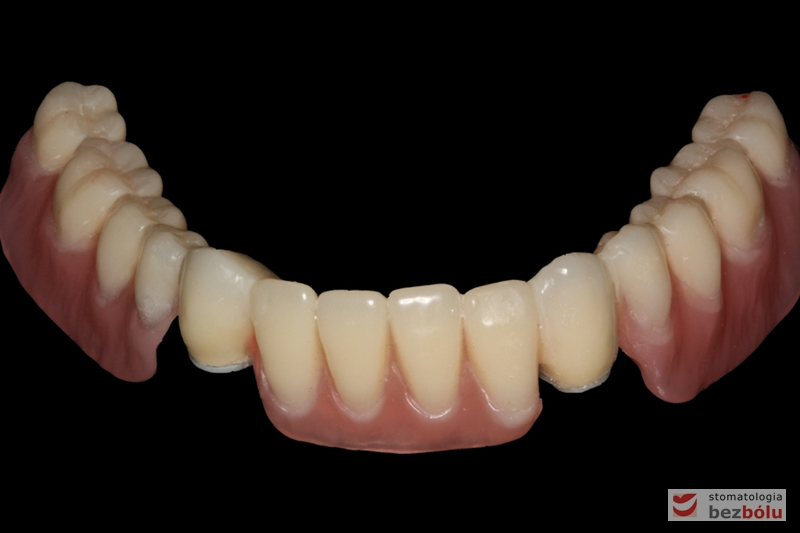

Odbudowa protetyczna żuchwy - wykonana przy użyciu zębów Michał Anioł Integrale

Odbudowa protetyczna żuchwy – wykonana przy użyciu zębów Michał Anioł Integrale